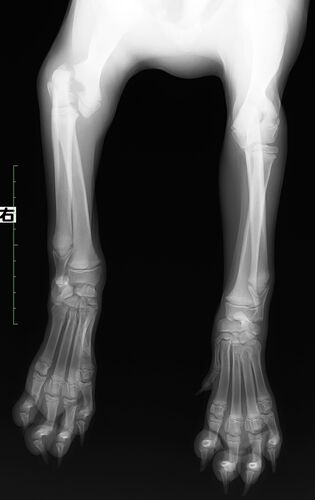

上腕骨遠位端骨折の犬の一例

症例は4か月齢、ゴールデンレトリーバーの女の子です。 階段から落ちたという主訴で来院されました。 レントゲンを撮ると右前肢の上腕骨遠位端骨折でした。 上腕骨の遠位端は若齢犬の骨折の好発部位となっています。若齢犬の骨には成長板という、骨の成長に…